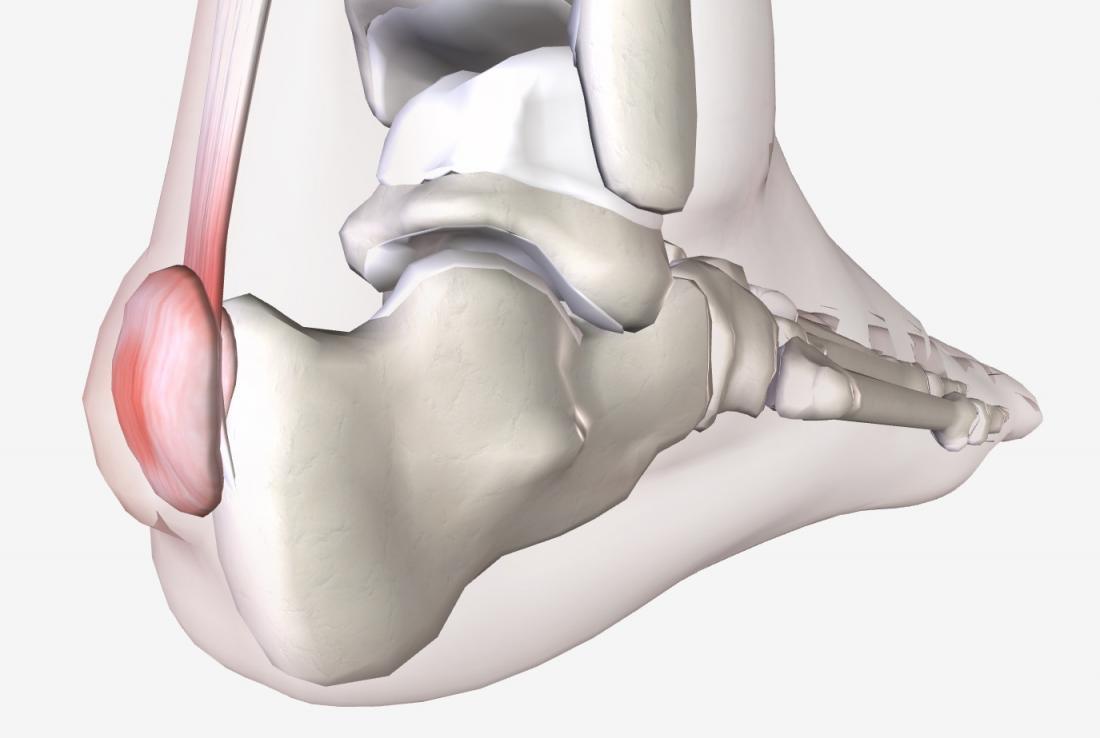

Haglund的畸形是指脚后跟的骨质增生肥大,当骨头的增大隆起后,后跟的皮肤反复摩擦到鞋子上时,跟腱附近的软组织(例如跟后滑囊)会受到刺激,导致滑囊炎,引起疼痛、皮肤发红等症状。

Haglund综合征一组临床征候群,表现为:足跟后上方跟腱止点处的无菌性炎症、骨性增生肥大以及皮下或跟腱下滑囊炎。该病变于1928年由Patrick Haglund首先描述,故将止点性跟腱炎、跟骨后上突增生(Haglund畸形)与跟腱滑囊炎统称为Haglund综合征。其中跟骨后滑囊炎好发于年轻人(30岁左右),而伴有骨赘形成的止点性跟腱炎则好发于年龄更高的人群。

Haglund畸形经常伴有跟腱炎,因为增生的骨赘会磨损跟腱,也会引起跟腱异常钙化,最终可能导致跟腱断裂。